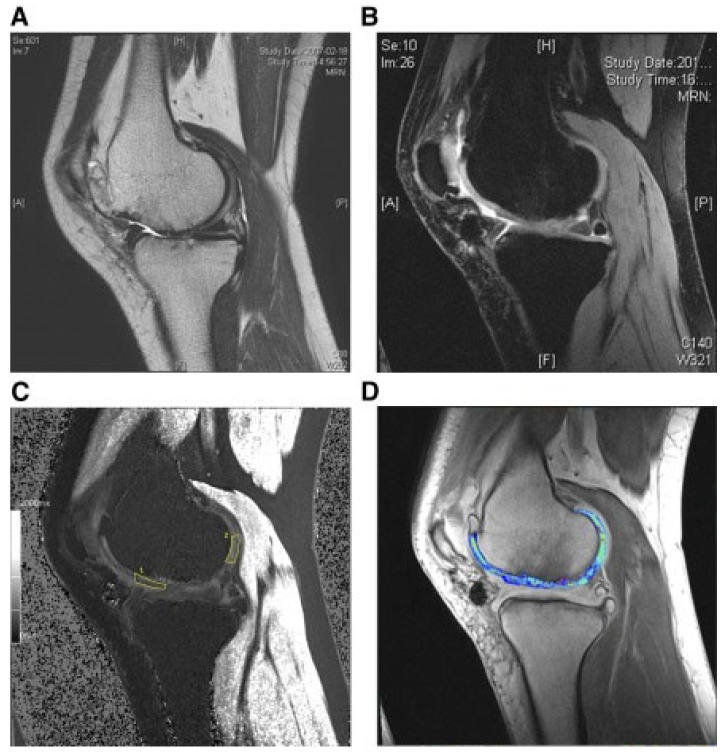

還評(píng)估了人臍帶血來(lái)源的間充質(zhì)干細(xì)胞(HUCB-MSC)治療軟骨再生的安全性和有效性。根據(jù)國(guó)際軟骨修復(fù)協(xié)會(huì)的數(shù)據(jù),HUCB-MSC用于治療7名患有KLIII級(jí)OA和IV級(jí)軟骨缺損的患者。同種異體HUCB-MSC在體外生長(zhǎng),然后與HA水凝膠結(jié)合并應(yīng)用于損傷部位。微骨折方案與這些細(xì)胞結(jié)合使用。12周后,修復(fù)的組織似乎成熟,24周后,臨床評(píng)分增加。在整個(gè)7年隨訪過(guò)程中,臨床改善的穩(wěn)定性也值得注意。組織學(xué)用于在手術(shù)后一年顯示透明軟骨,而MRI用于在手術(shù)后3年顯示軟骨再生,如圖所示圖3(其中釓-DTPA用作造影劑,以藍(lán)色顯示)。

圖3:HUCB-MSC治療后3年軟骨再生的MRI評(píng)估

(A) 術(shù)前軟骨缺損。(B) 移植后3年軟骨再生。(C) 通過(guò)在標(biāo)記區(qū)域采樣來(lái)計(jì)算相對(duì)軟骨松弛率的變化。(D) 顯示與藍(lán)色信號(hào)相關(guān)的GAG含量增加。